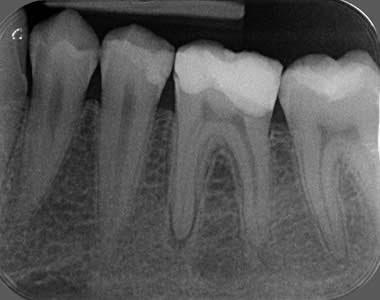

PERİAPİKAL RÖNTGEN

Periapikal röntgen, sıkça tercih edilen bir ağız içi görüntüleme yöntemi olup, dişler ve çevresindeki kemik yapıları hakkında detaylı bilgi sunar.